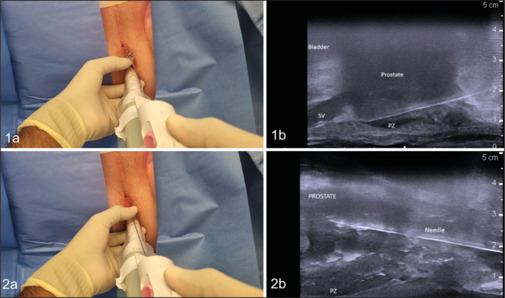

Introduction: Transperineal access systems are commonly used to stabilize the biopsy needle with the ultrasound probe in local anesthetic transperineal biopsies (LATPs). However, these devices are expensive and nonreusable and restrict the access to some of the prostatic zones causing excessive probe movement and procedural pain. We aim to assess the pain tolerability, diagnostic value, and safety of the totally freehand LATP (tF-LATP) technique.

Methods: Patients undergoing tF-LATP for suspected prostate cancer (PCa) from February 2024 to June 2024 were prospectively included. Data on the prostate-specific antigen (PSA) levels, prostate size, prostate multiparametric magnetic resonance imaging findings, cancer detection, need for immediate rebiopsy due to undersampling (with predefined criteria for immediate rebiopsy), tolerability, and complications were collected. Pain levels were assessed using the Visual Analog Scale (VAS) scores (scores 1-10) at rectal probe insertion and immediately postbiopsy.